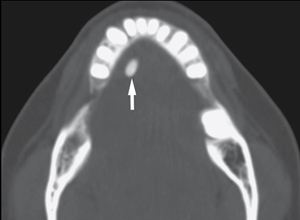

涎石病是指發(fā)生在涎腺腺體及其導(dǎo)管中的鈣化性團塊而引起的一系列病變。下頜下腺涎石最常見,腮腺次之。涎石常使唾液排出受阻,并繼發(fā)感染,造成腺體急性或反復(fù)發(fā)作的炎癥??梢娪谌魏文挲g,以20~40歲的中青年人多見。男性多于女性,病程短者數(shù)天,長者數(shù)年甚至數(shù)十年。